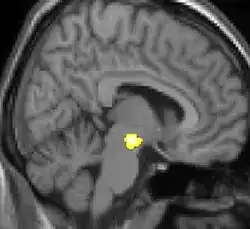

Example of a VBM analysis on patients who experience cluster headaches.

Voxel-based morphometry is a computational approach to neuroanatomy that measures differences in local concentrations of brain tissue, through a voxel-wise comparison of multiple brain images.[1][2] In traditional morphometry, volume of the whole brain or its subparts is measured by drawing regions of interest (ROIs) on images from brain scanning and calculating the volume enclosed. However, this is time consuming and can only provide measures of rather large areas. Smaller differences in volume may be overlooked. The value of VBM is that it allows for comprehensive measurement of differences, not just in specific structures, but throughout the entire brain. VBM registers every brain to a template, which gets rid of most of the large differences in brain anatomy among people. Then the brain images are smoothed so that each voxel represents the average of itself and its neighbors. Finally, the image volume is compared across brains at every voxel.